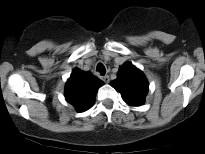

问题 男,68岁,呼吸困难、轻度吞咽困难3月余,请结合CT,选择最可能的诊断 ( )

选项 A.气管乳头状瘤 B.气管脓肿 C.气管炎性假瘤 D.食管癌 E.甲状腺癌

答案 A